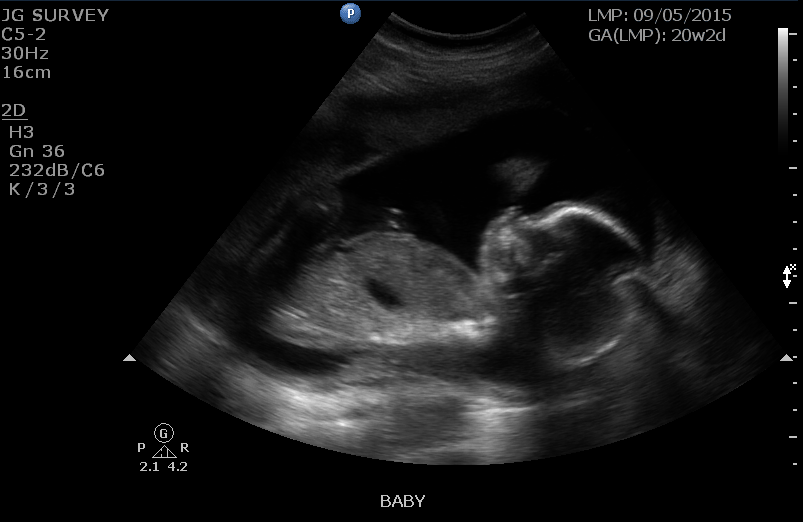

I finally get to post on this thread!! Had our first ultrasound yesterday at 20+2 and got to see the little ninja for the first time. We are in love! Team green here.

I love the 20-week scan! Baby clearly looks like a real baby and still all fits on the screen. We are team green, but baby's legs were crossed anyway (you can see the feet together at the top left). The tech also said he/she had its boxing gloves on because its hands were up by its face, but every once in a while the face would poke out. So much fun and super cute!